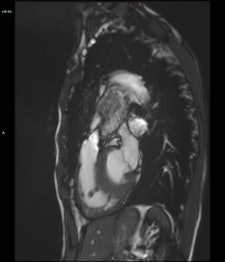

![Cardiac MR of a 59-year old patient carrying an implantable cardioverter defibrillator (ICD). The cine steady state with free precession sequence (time of repetition [TR] 50 ms, time to echo [TE] 3.3 ms, flip angle 80°) acquired along the four-chamber view (a) was largely impaired by a large concentric artifact (asterisk in a) not allowing for segmenting both ventricles. The corresponding cine gradient echo fast low-angle shot sequence (b) (TR 49 ms, TE 1.5 ms, flip angle 15°) shows a strongly reduced artifact generated by the ICD not impairing the evaluation of both ventricles. The artifact generated by the electro-catheter is visible in the right atrium in both images (white arrows in a and b). Image courtesy of Moreno Zanardo.](https://img.auntminnieeurope.com/files/base/smg/all/image/2017/11/ame.2017_11_15_16_20_6001_2017_11_13_MRI_insider_pic11_20171115163055.png?auto=format%2Ccompress&fit=max&q=70&w=400)